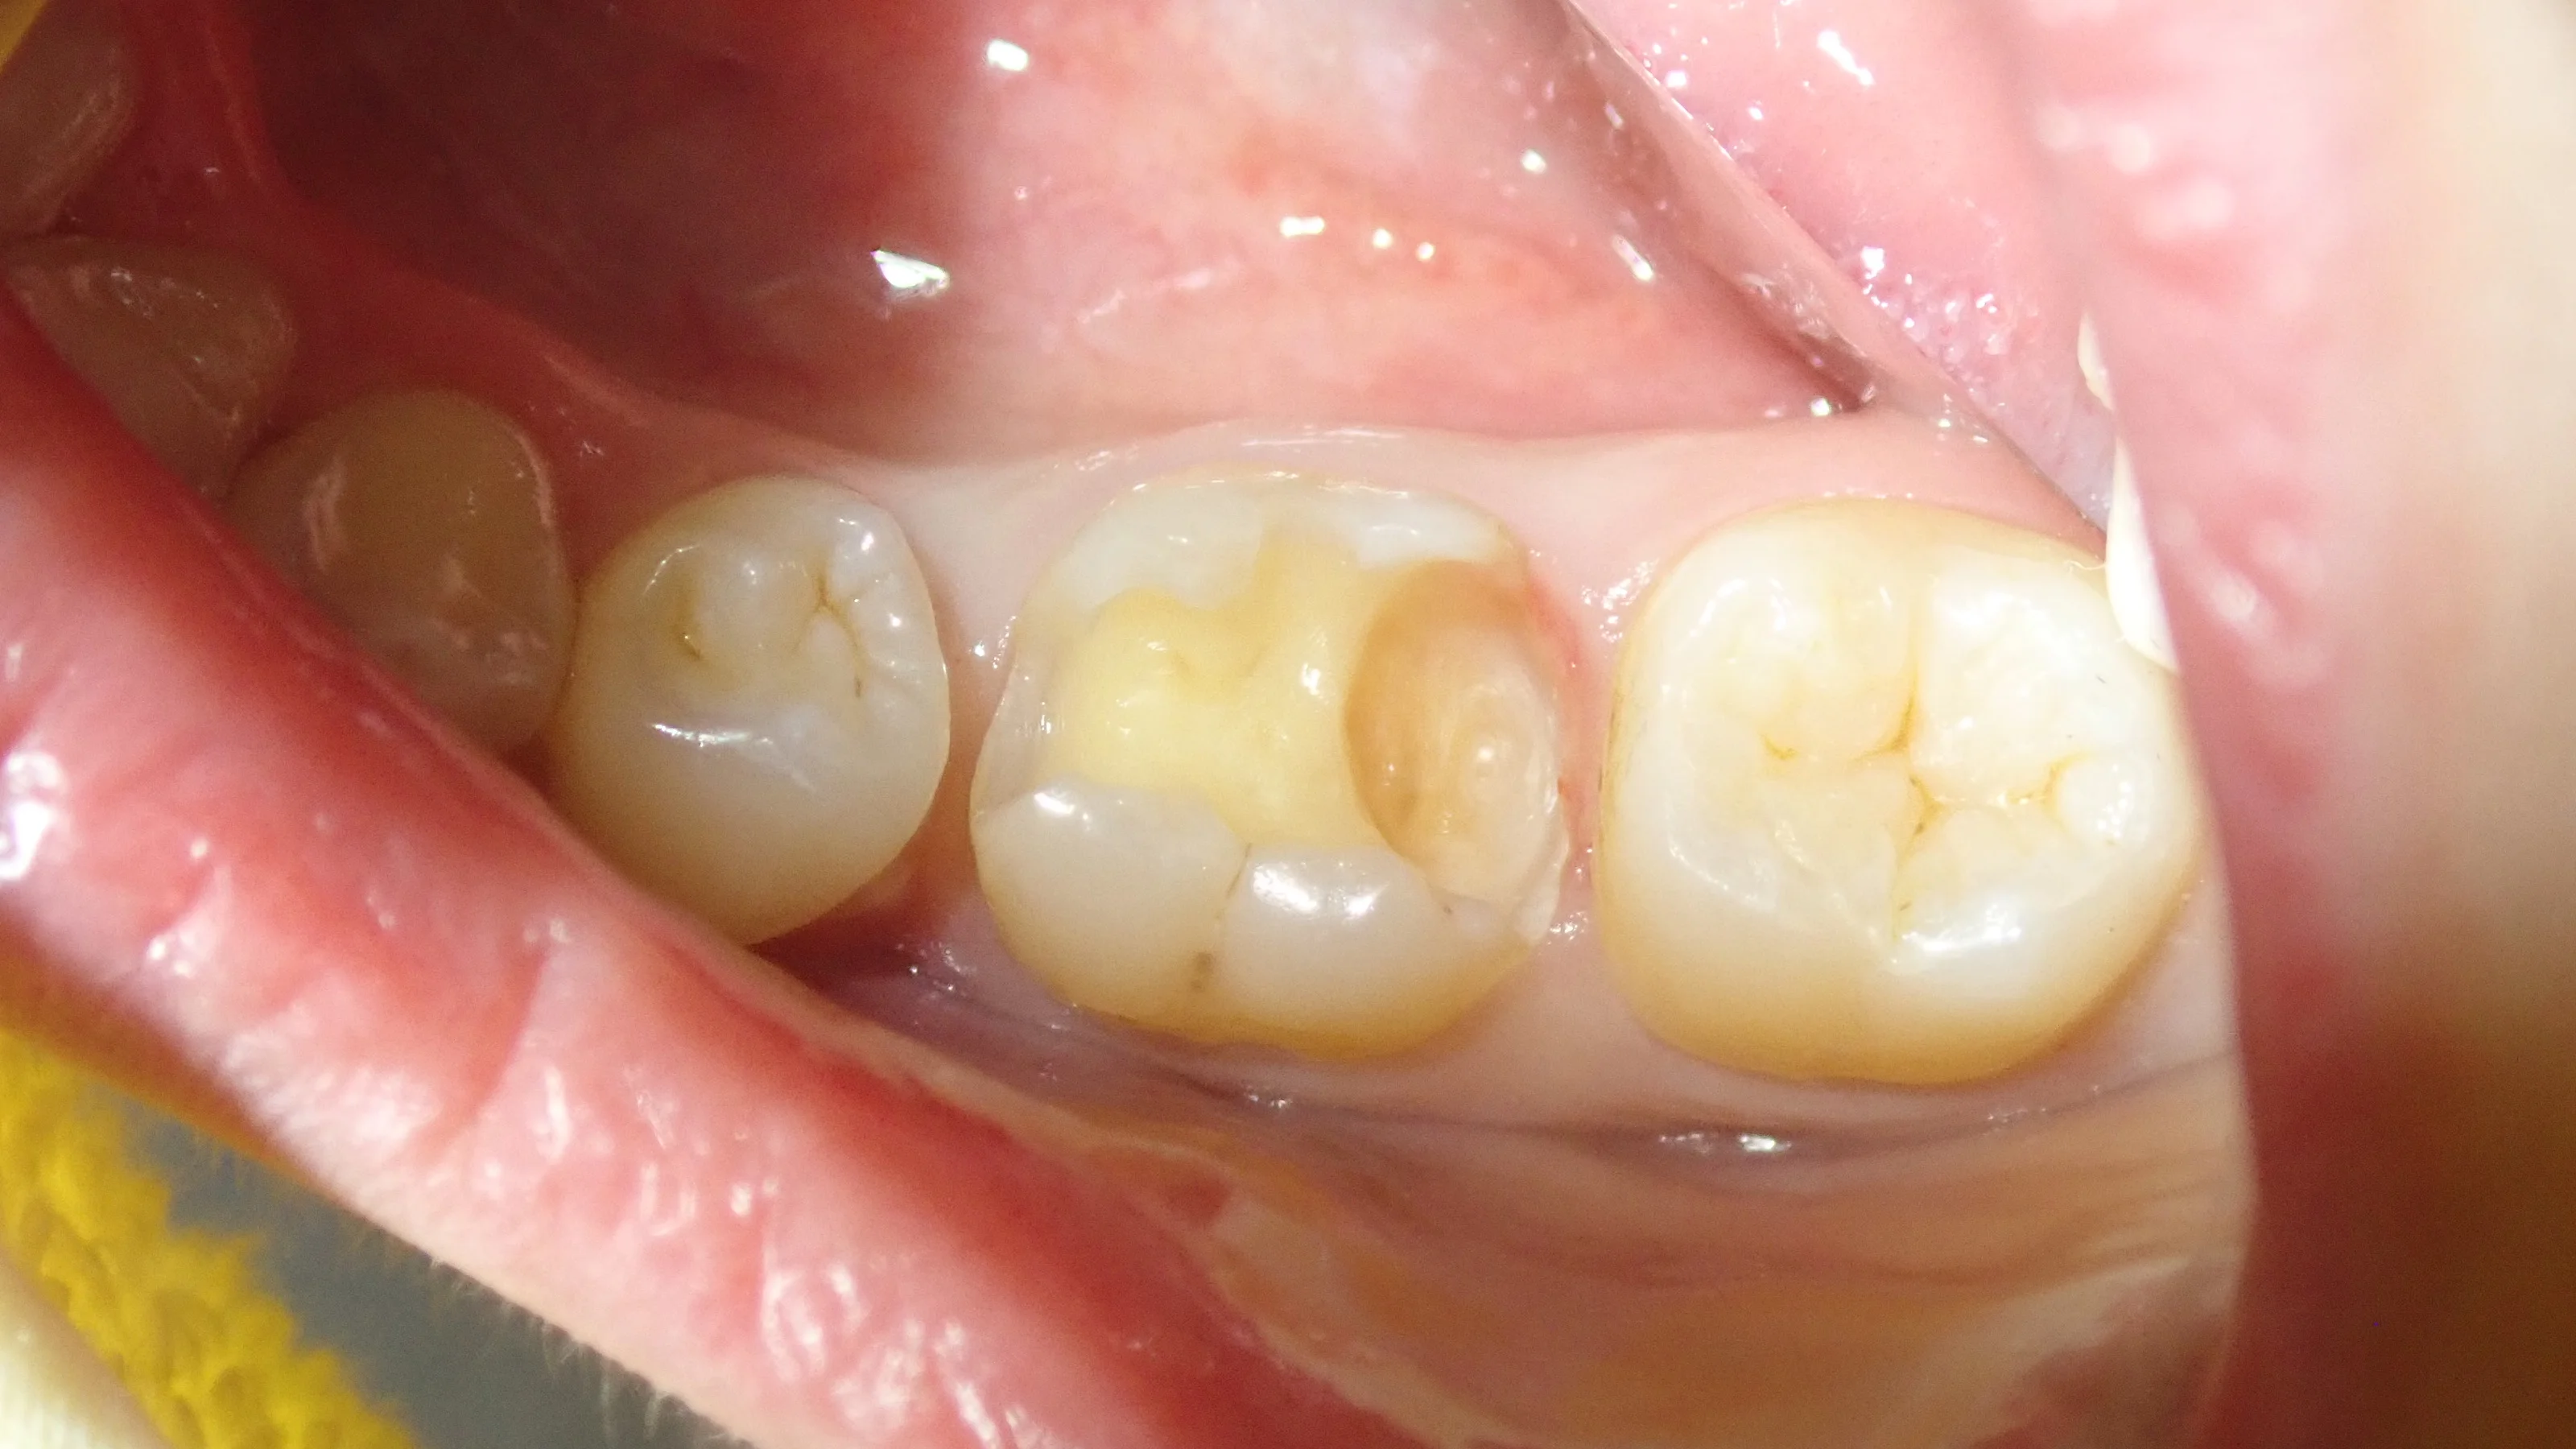

そして、詰め終わったのがこちら

奥2本のダイレクトボンディング|坂寄歯科医院(取手市藤代) - 画像7

スペースが非常に大きかったため、半ば無理矢理スペースを埋めました。

歯科医療従事者の方なので、ブラッシングなどはしっかりと行ってもらえるでしょう・・・!

終わった後の写真を見て、非常に喜んでいただけて良かったです!

しっかりと歯磨き・フロスなどを頑張って、なるべく長持ちさせていただきたいですね!